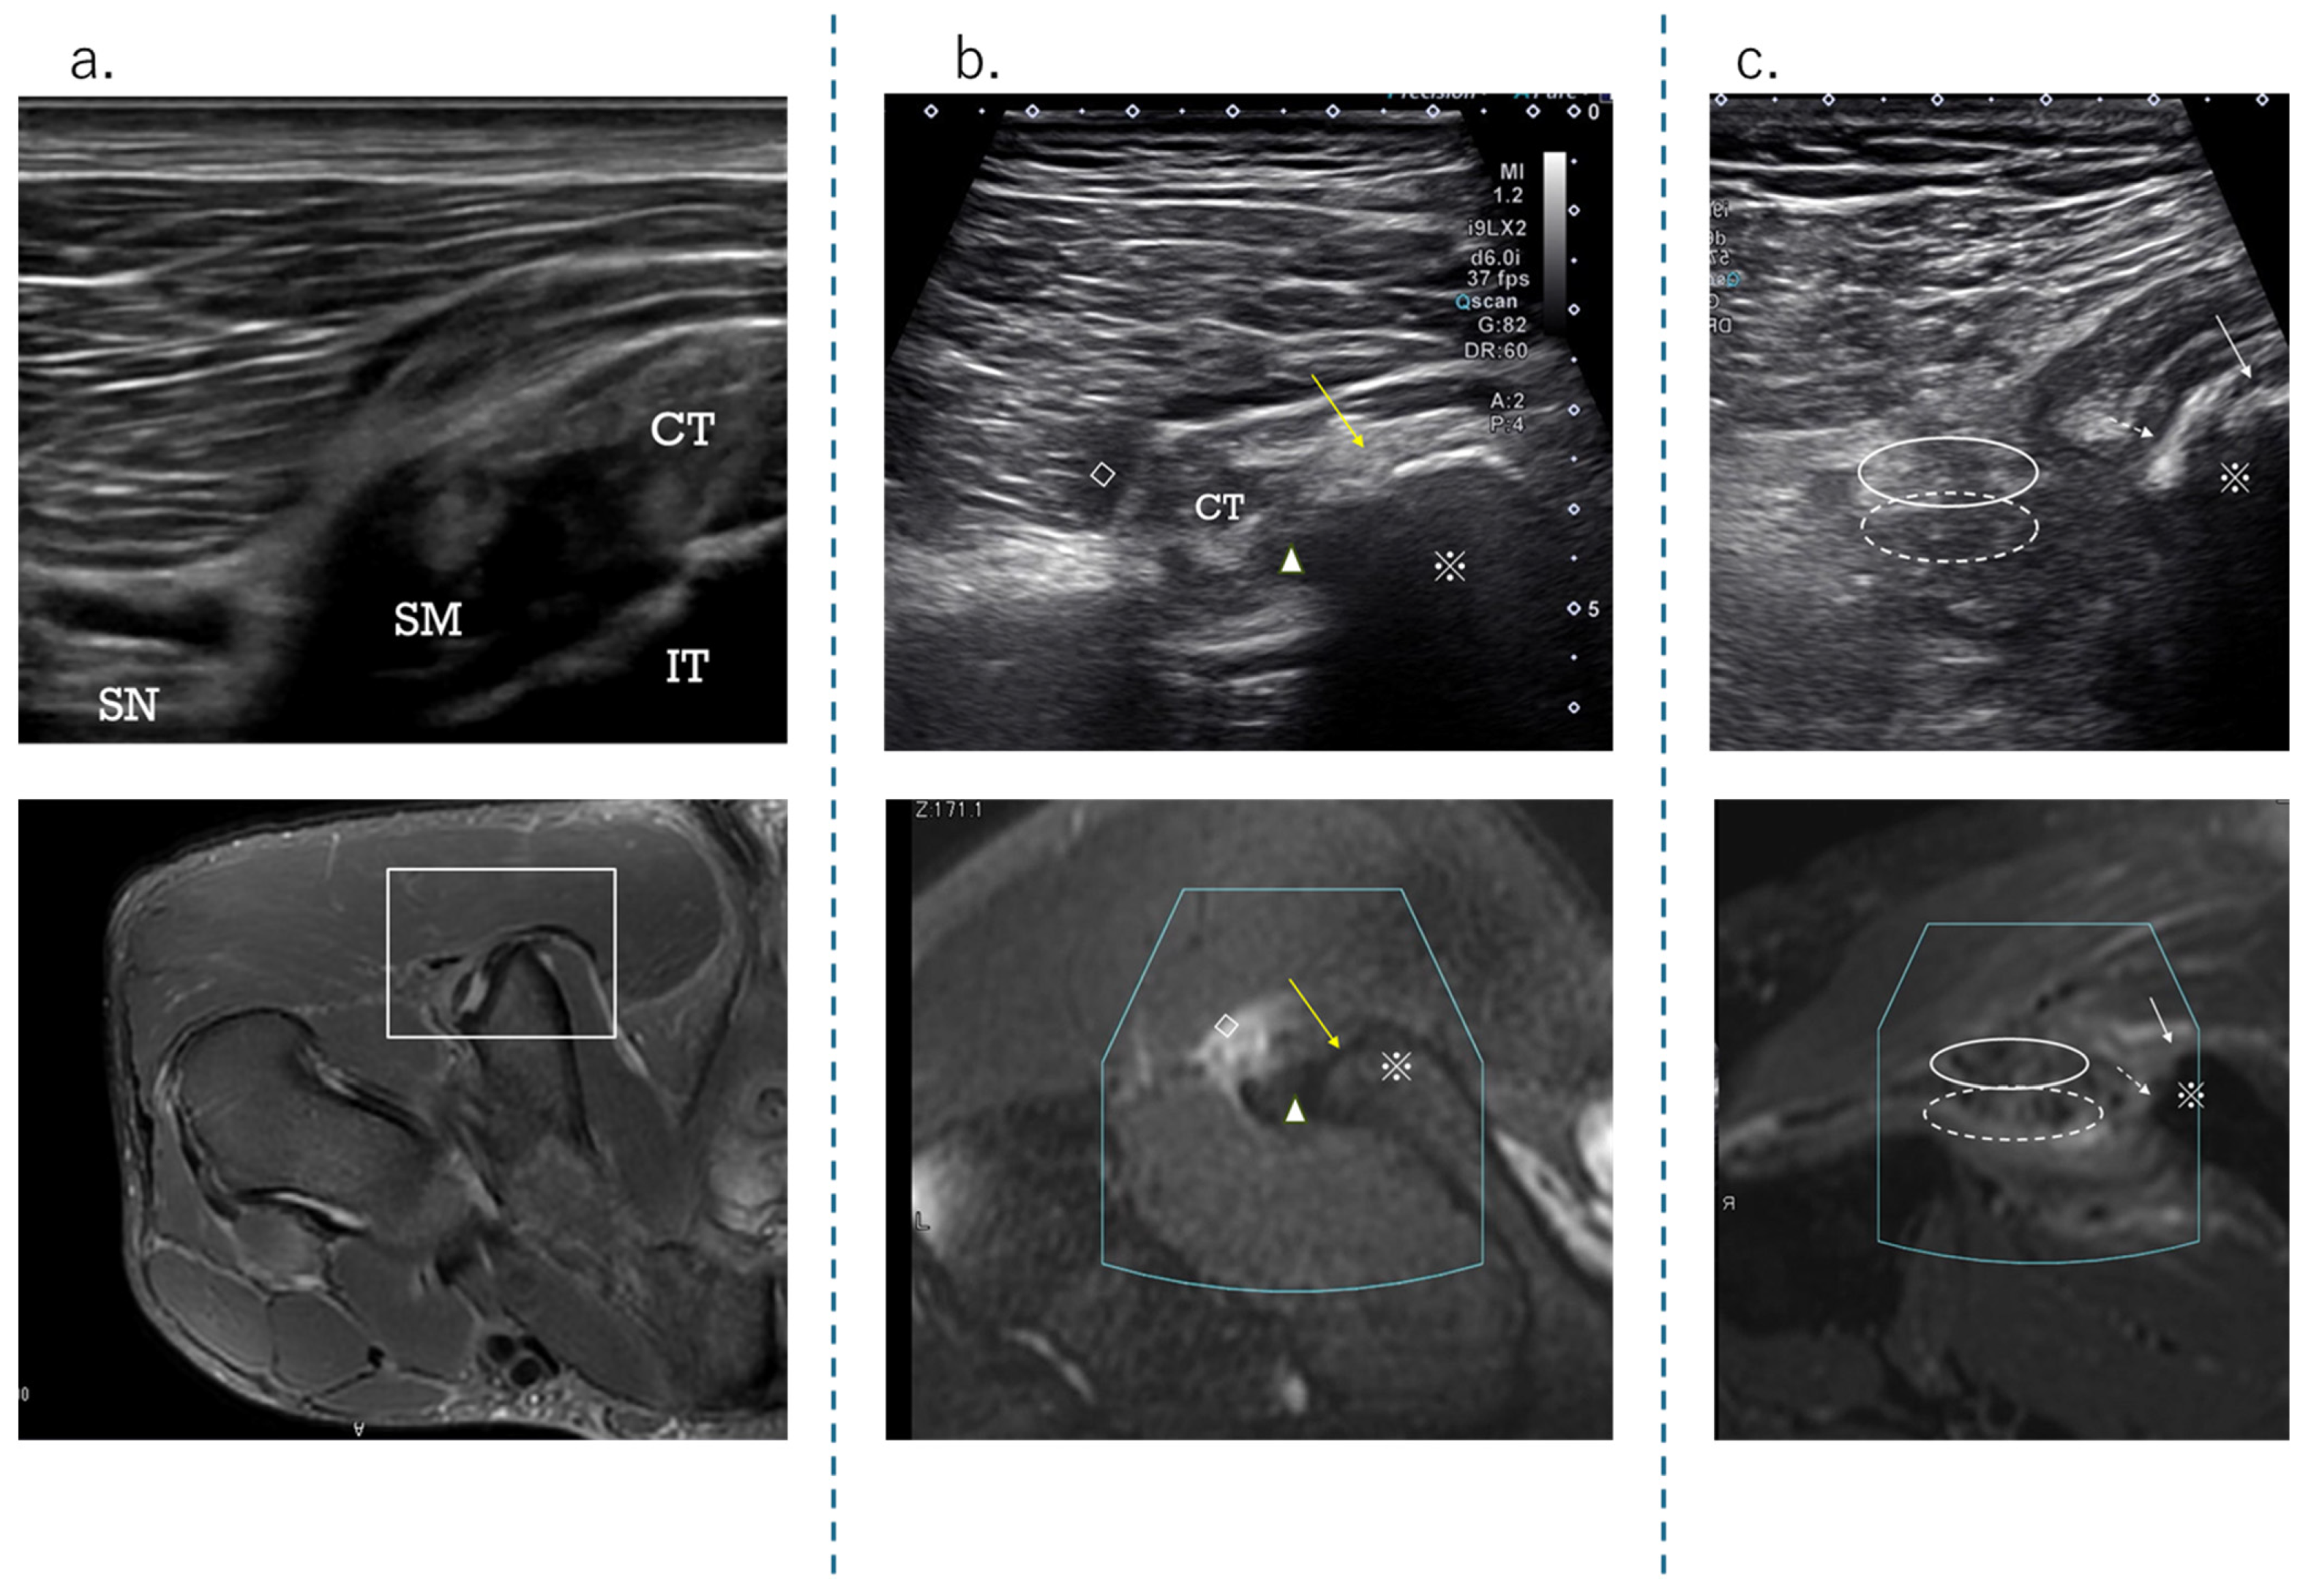

Figure 4. Short-axis view at the level osteotendinous junction at ischial tuberosity. (a) Schema showing the attachment of the ischial tuberosity; (b) normal ultrasound short-axis image of the ischial tuberosity attachment; (c) normal axial image (T2-weighted image with fat suppression) taken using MRI.

Figure 5. The US findings (upper row) and MRI images (lower row) of the originate tendon detachment at ischial tuberosity. (a) Detached image of the SM tendon attachment; (b) detached image of the CT attachment (yellow arrow), hematoma (white square), and SM attachment (solid white triangle); (c) detached image of the CT attachment (white arrow) and CT (white ellipse), detached SM attachment (white dashed arrow), and SMT (white dashed ellipse). Diagnostics 15 00054 i001: Ischial tuberosity.

The HMC is a biarticular muscle complex made up of four muscles, three of which originate from the ischial tuberosity with the CT and SMT. The ST is composed of muscle fibers that originate both directly from the ischium and from the conjoint tendon (CT), whereas all BFLH muscle fibers originate from the CT [2,3,8,10] (Figure 2a). Type I injuries are defined as a tear of the CT. As in the diagnostic procedure described above, by carefully observing via ultrasound, it is possible to determine the location of the damage. When performing an ultrasound evaluation of damage to the ischial tuberosity and surrounding area of the origin tendon, such as in CT and SMT, it is easier to see the detached and coiled appearance of the damaged tendon and find swelling if the evaluation is performed at the level where the CT and SMT intersect (Figure 2a, dashed line). The characteristics of the ultrasonic short-axis findings in cases of CT injury and SMT injury and injury to both the CT and SMT are shown in Figure 3. The position of the attachment points of the SMT, CT, and ST muscle fibers are important. The SMT runs through the deep layer of the CT and attaches to the lateral side of the ischial tuberosity. The CT attaches to the medial side of the SMT, and the muscle fibers of the ST attach further to the medial side. The area where the SMT attaches is difficult to visualize using ultrasound in athletes with well-developed gluteal muscles or those with a lot of subcutaneous fat. In such cases, it is useful to evaluate by scanning from the points in Figure 2 and Figure 3 towards the proximal end. The short-axis image of the ischial tuberosity is shown next, in contrast to the MRI image (Figure 4 and Figure 5). In this study, detection by ultrasound was possible for both the BF-ST complex and SM in all but one case, which was a minor injury without conjoint tendon tortuosity or hematoma.